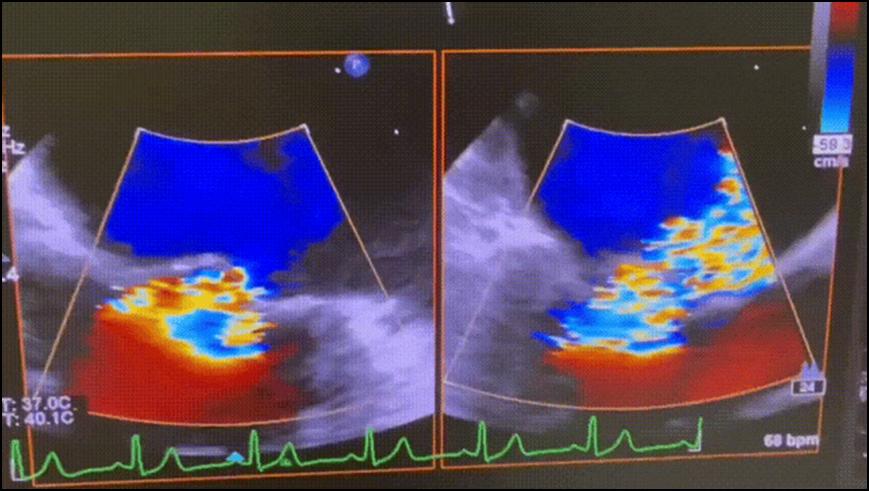

劉海波主任團(tuán)隊(duì)術(shù)前經(jīng)過反復(fù)推演手術(shù)流程并制定應(yīng)急預(yù)案。手術(shù)當(dāng)天,在心臟彩超的“精確制導(dǎo)”下,僅通過一個小針眼,順著血管將一枚小巧的二尖瓣夾送至心臟病變部位。隨著夾子精準(zhǔn)夾合,患者的二尖瓣反流量瞬間大幅減少——整個手術(shù)過程順利,創(chuàng)傷極小。術(shù)后患者胸悶、氣短癥狀明顯緩解,經(jīng)復(fù)查二尖瓣反流程度由“極重度”降至“輕度”,術(shù)后1周便順利出院?;颊呒凹覍賹χ委熜ЧB連稱贊。

<<>二尖瓣鉗夾示意>

<<>術(shù)前,二尖瓣反流(大量)>

<術(shù)后,二尖瓣反流(少量)>